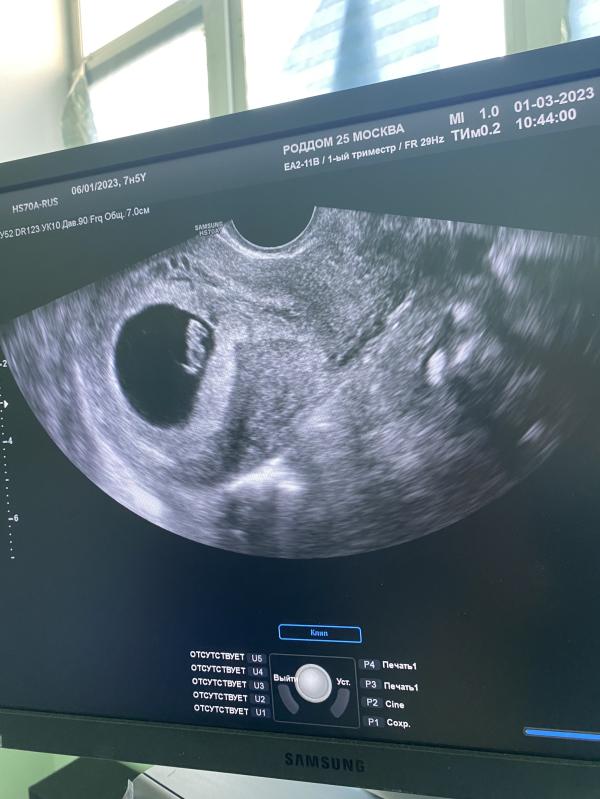

УЗИ подтвердило: сердечко бьется, креветочка растет! Делюсь радостью и подробностями

Была сегодня узи: сердечко стучит, креветочка растет 🥰

На счет роддома не знаю, но моя жк (в ней узи делала) раньше к нему относилась, а сейчас к коммунарке…мб в программе не сменили